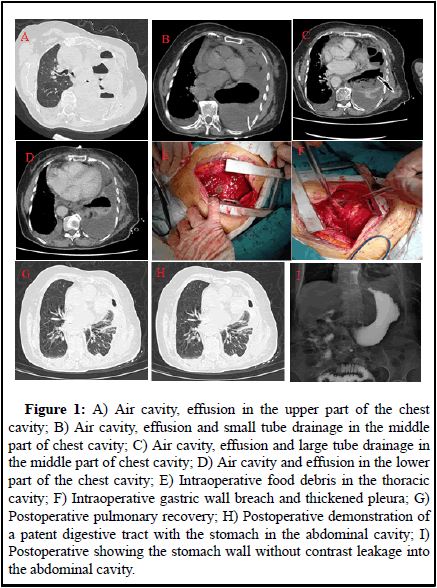

The left lung was turbid by percussion and the chest tube was unavailable. Computed Tomography (CT): Atelectasis of the left lung, structures in the left hilar region was poorly displayed and soft tissue shadows appeared to be seen in the hilar region. There was a large amount of fluid and air in the pleural cavity on the left side, with a drainage tube placed in it and there was a small amount of fluid in the pleural cavity on the right side. Pneumothorax changes on the right side. Small amount of pericardial effusion (Figure 1A, B). Blood count: Leukocytes 16.36 × 10/L, hemoglobin 105 g/L, neutrophil ratio 80.50%, lymphocyte ratio 8.10%, albumin 26.2 g/L, calcitonin 0.569 ngmL [3].

• Pericardial treatment: anti-infection treatment was given after admission, placement of a large tube of closed chest drain (Figure 1C, D), a small amount of yellowish liquid was drained. Pathological diagnosis of pleural fluid: Found most of the inflammatory cells mainly neutrophil, did not see the exact tumour cells [4].

During surgery, extensive adhesions were found in the right thoracic cavity, with thickening of the dirty pleura and the wall pleura, up to about 1 cm. Food debris was seen in the thoracic cavity (Figure 1E). There were multiple septate and encapsulated pus cavities. The diaphragm showed a 3 × 5 cm fissure and the gastric fundus entered the thoracic cavity and became embedded and ischemic necrosis. There were three necrotic perforations in the gastric wall of about 1 × 1 cm, 3 × 3 cm and 3 × 4 cm respectively (Figure 1F). Surgical method: Lung decortication+diaphragmatic repair+partial gastrectomy. Surgical incision: left posterior lateral sixth intercostal incision of about 20 cm. Chest pus culture showed Candida glabrata. Postoperatively, she was given parenteral nutrition, blood transfusion, anti-infection, correction of liver function, antifungal and symptomatic treatment. After surgery, her heart function failed, with positive treatment, her condition improved. She was discharged from the hospital 2 weeks after the operation (Figure 1G, H, I) [6].

Figure 1: A) Air cavity, effusion in the upper part of the chest cavity; B) Air cavity, effusion and small tube drainage in the middle part of chest cavity; C) Air cavity, effusion and large tube drainage in the middle part of chest cavity; D) Air cavity and effusion in the lower part of the chest cavity; E) Intraoperative food debris in the thoracic cavity; F) Intraoperative gastric wall breach and thickened pleura; G) Postoperative pulmonary recovery; H) Postoperative demonstration of a patent digestive tract with the stomach in the abdominal cavity; I) Postoperative showing the stomach wall without contrast leakage into the abdominal cavity.